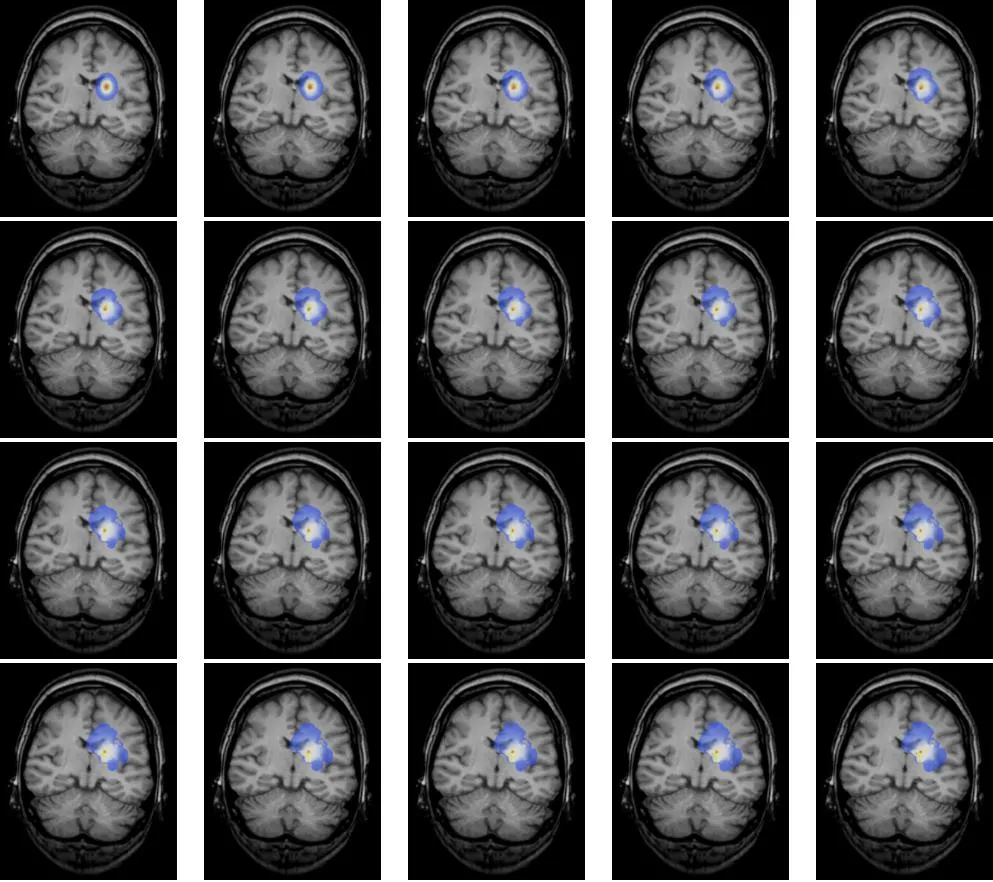

四级胶质瘤影像图

国外的脑科学曾利用扩散生长模型模拟脑肿瘤生长,并得出如下图像,它演示了一个本来边界清晰、影响范围不算特别大的脑瘤经过一段时间的发展可能会演变成边界不清、波及范围更广的全过程,这也说明了肿瘤不仅会生长,还极有可能升级恶化!